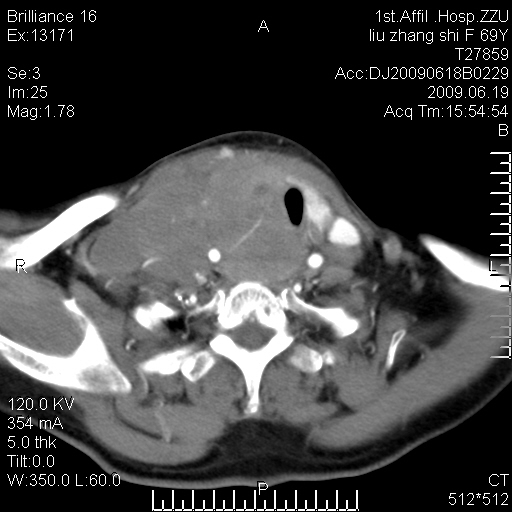

标题: CT26782:女,69岁,颈部占位,3天后公布病理结果。

【病理证实系列】女,69岁,颈部占位,有病理结果,3天后公布。(由于病例时间较久,临床资料不全,请网友见谅)本系列将有几百种常见、少见及罕见病例,均经病理证实。病例资料来自郑州大学第一附属医院。与网友共享,本人有空就发。

甲状腺癌并颈部淋巴结转移。感谢楼主的良苦用心,谢谢。

甲状腺癌并颈部淋巴结转移。

需与鼻咽癌鉴别!

支持甲状腺癌广泛侵及周围结构并颈部淋巴结转移。

鉴别:淋巴瘤、恶性神经源性病变、恶性纤维组织细胞瘤。

病理结果:颈部非霍奇金淋巴瘤。

右侧甲状腺确实有问题